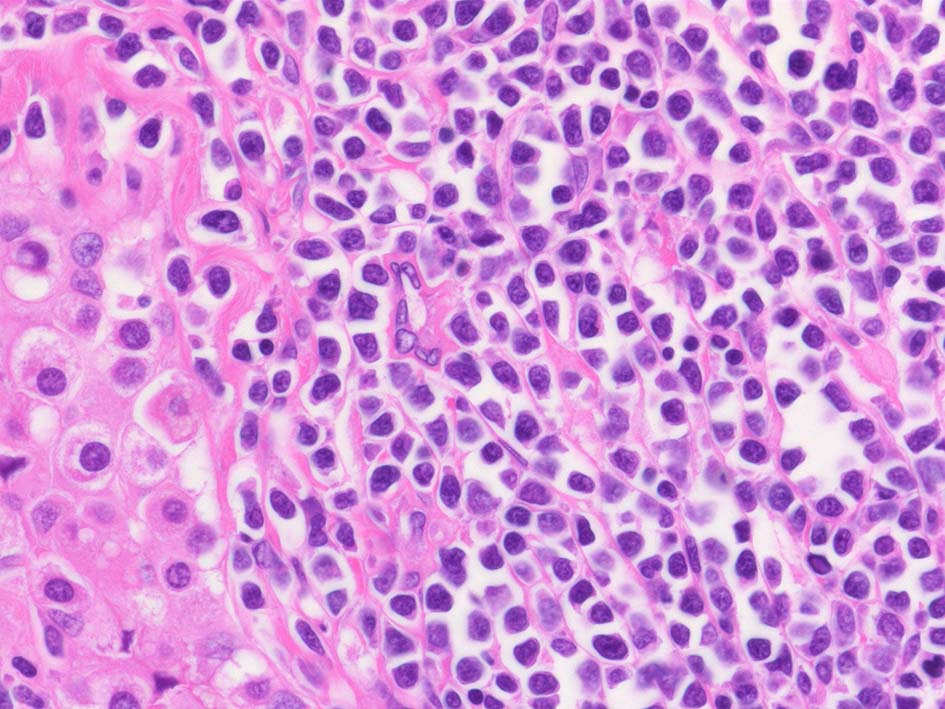

類円形/多稜形の核をもつN/C比大の細胞. 粗大なクロマチンが増加, 核小体は不明瞭. DLBCLに認められるcentroblasts/ immunoblastsの細胞所見と異なる.

LCA(CD45)+, CD20+(focalに陰性), CD79a+, PAX5+, CD5-, CD10+, BCL6+が多い, MUM1-, BCL2+, cyclinD1-, MIB1 LI; very high(>80%). EBER-ISH-.

IGH; clonal band+ (BIOMED2, FR1 and FR2). MYD88L265PはAS-specific PCRで陰性. Molecular にもcommon typeのtesticular DLBCLとは異なっているようである.